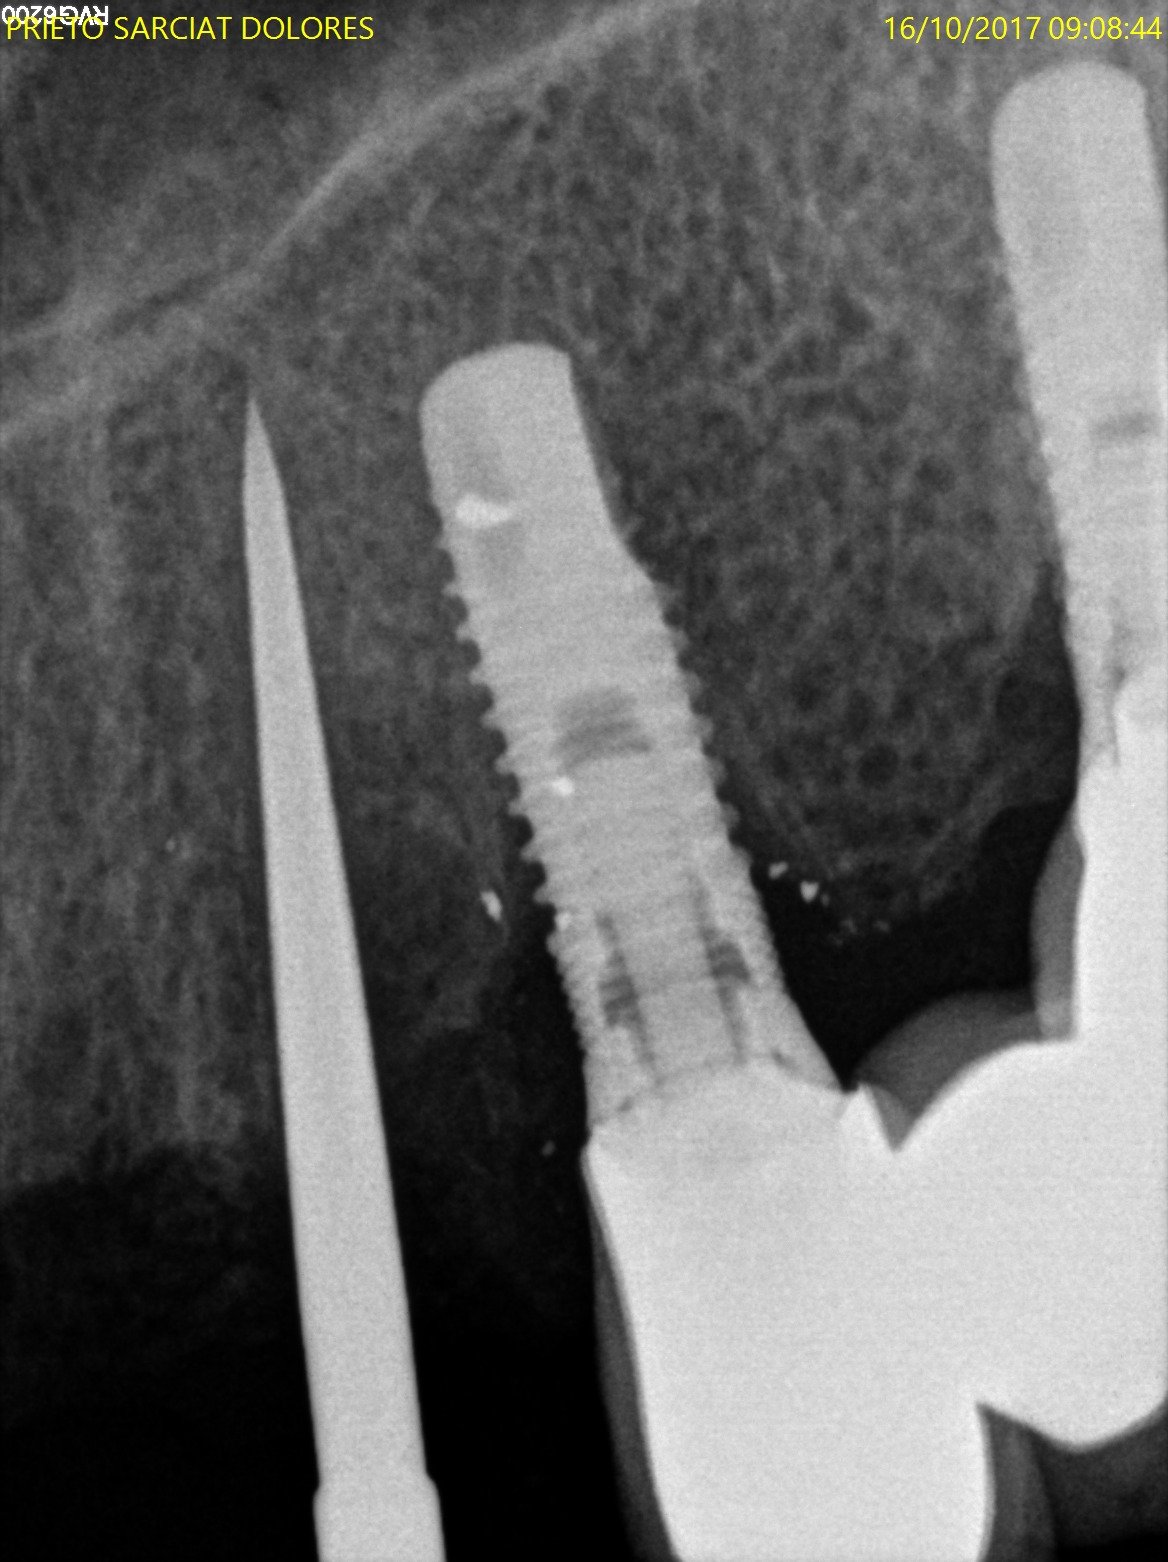

Implante pza 4.6, instalado hace 8 años en Chile, el paciente no sabe que marca es, se encuentra con tapa de cierre, y se desatornillo con llave 0,48. El diámetro [...]